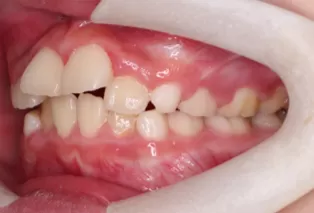

Photos intra-orales